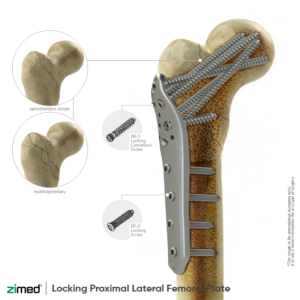

Large Fragment Locking Plate System

Locking Proximal Lateral Femoral Plate